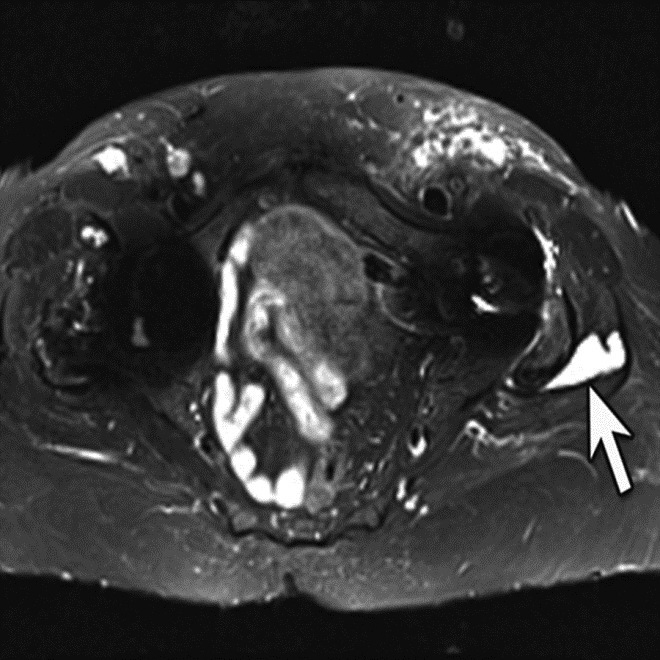

| Inversion Recovery Imaging. (B) Axial STIR MR image in the same patient reveals fluid-signal pseudotumor (arrow) adjacent to the left greater trochanter, which was obscured on prior examination. |

Adverse reaction to metal debris with posterior pseudotumor. Axial T1-weighted fast spin echo (FSE) (A) and STIR (B) MR images demonstrate left peritrochanteric fluid collection (arrow in A and arrowheads in B) arising from the left hip joint in a patient with metal-on-metal hip arthroplasty. Note the thin low T2 signal rim surrounding the fluid collection representing metal deposition. |